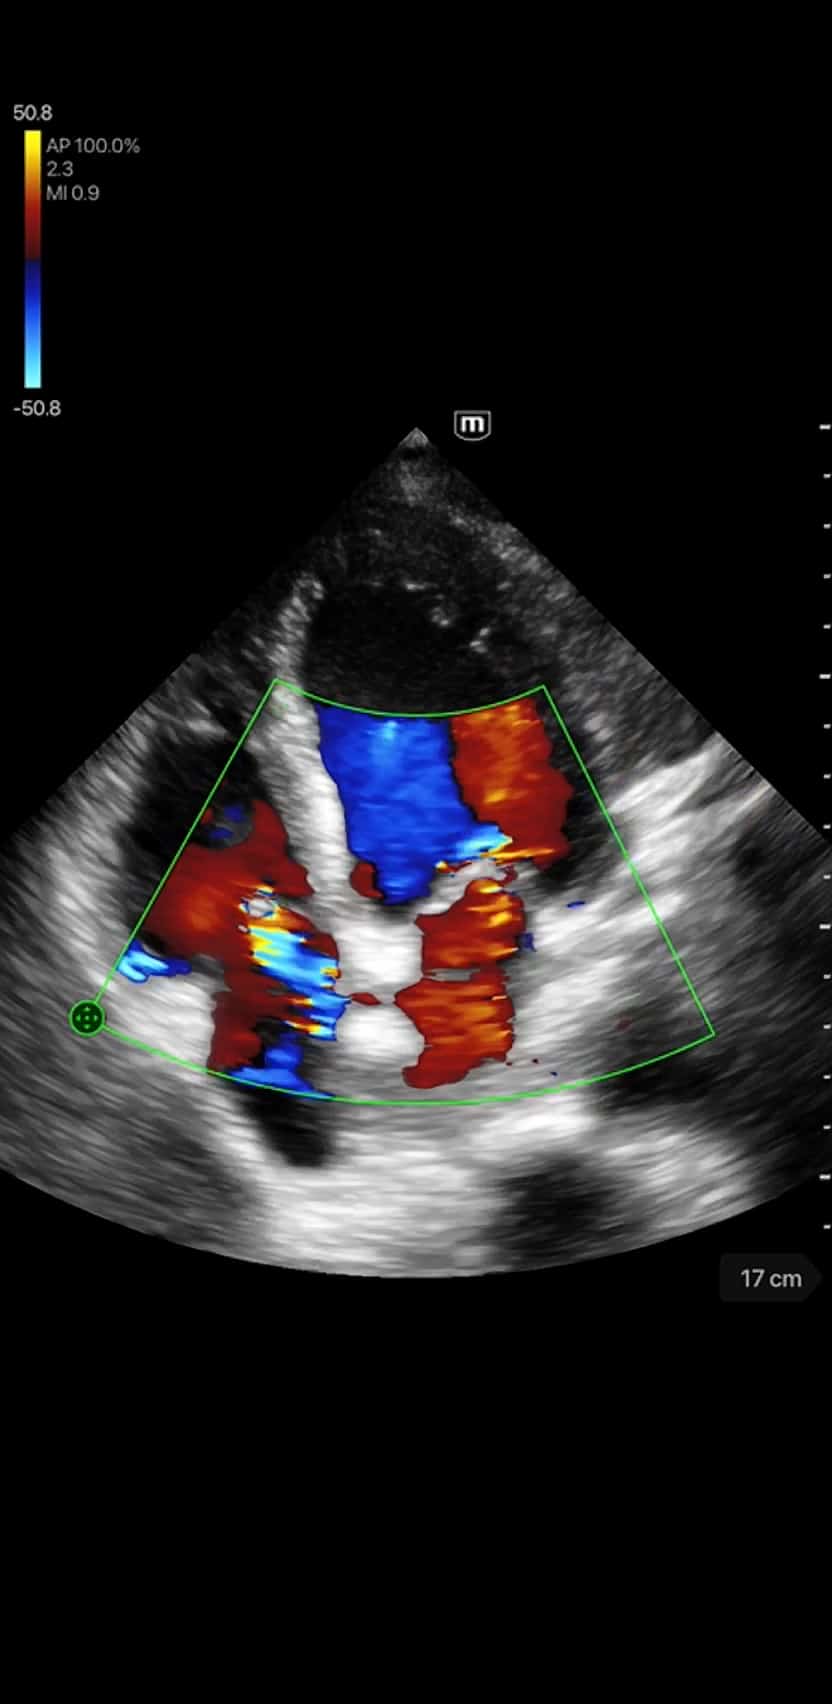

- Scanning modes: B-mode, M-mode, Color Doppler, Power Doppler, PW, and Tissue Doppler Imaging

- Dedicated presets for Cardiac, Abdomen, Lung, Transcranial Imaging (TCI), Emergency Medicine (EM), Trauma (FAST), EM Abdominal

- Aortic Aneurysm (AAA), Bladder, OB/GYN, and Vascular

Clinical Images